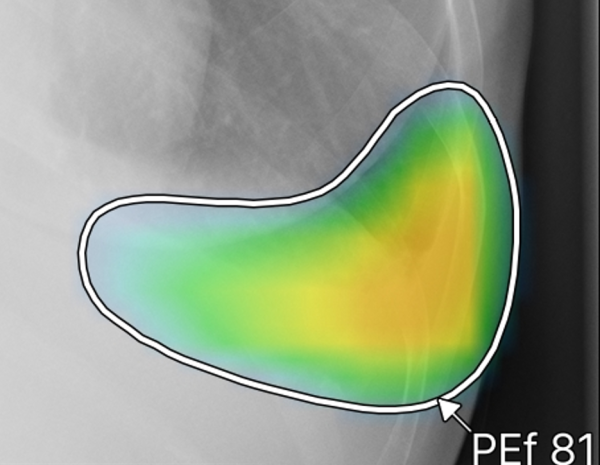

ヒートマップ/輪郭表示機能

異常所見の存在可能性(確信度)を、青から赤へのグラデーションで示すヒートマップ表示について、多くの利用者からご好評いただいている。一方、モノクロモニタを利用する一部の読影環境では、淡いヒートマップが確認しにくいという課題があった。新バージョンでは、異常所見の疑われる領域の表示方法として、「ヒートマップ表示」「輪郭表示」「ヒートマップと輪郭の併用表示」の3つの表示パターンが選択可能になった。これにより、各施設の運用環境に応じた最適な表示方法を利用できる。

従来のバージョンでは、複数の異常所見を検出した場合、検出された異常所見のうち最も確信度が高い所見のスコアのみを表示しており、各所見のスコアを確認したいという要望があった。新バージョンでは、各検出領域に対応する所見名と確信度を示すスコアを個別に表示できるようになった。これにより、医師は複数の異常所見について詳しい情報をひと目で把握でき、正確な診断を行うことが期待できる。

また、従来のバージョンでは、対象所見が重なった領域においてヒートマップが重なって表示されていまた。そのため、異なる所見が混在している部分の識別が難しく、細かな判別や詳細な確認には限界があった。これに対し、新バージョンでは、対象所見が重なった領域についても、各所見ごとに独立した輪郭線を表示できるようになった。複数の異常所見が存在する箇所でも、それぞれの所見の範囲を明確に区別できるようになり、より詳細かつ正確な画像診断支援が期待される。